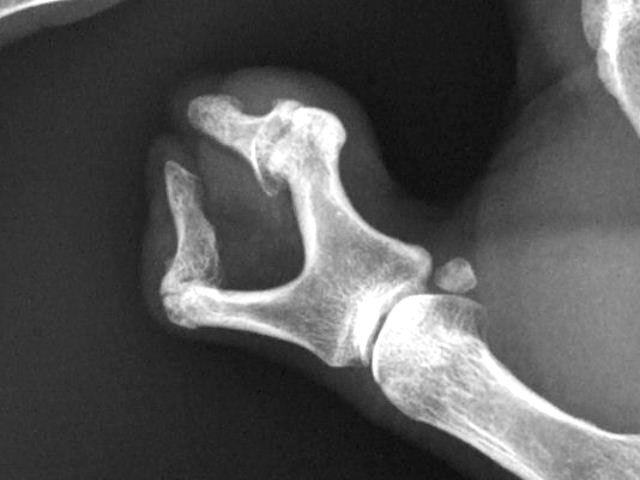

Carpo normal